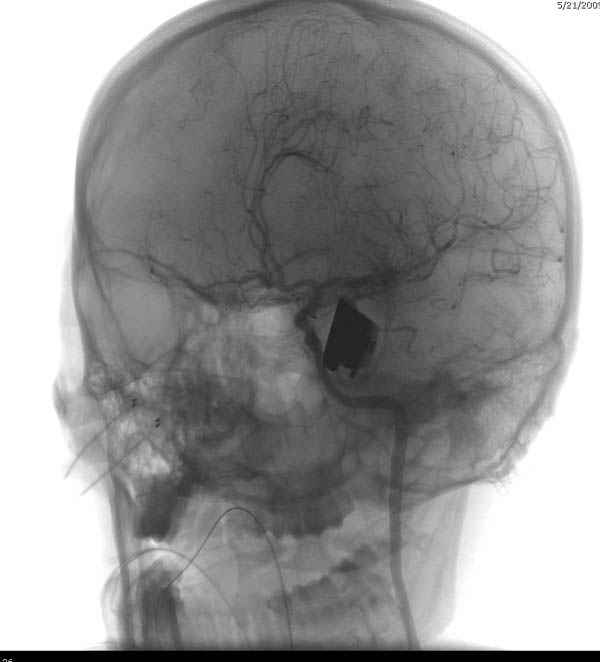

По протоколу сделаны все необходимые исследования: рентген, ангиограмма с 3Д реконструкцией, где обнаружили что все жизненно важные сосуды не задеты, даже некоторые "сидят" изгибаясь на ноже.

Одним махом нож удалить не удалось, пришлось раскачать и потом двумя руками удалили нож. Рана без кровотечения, обработана и зашита.